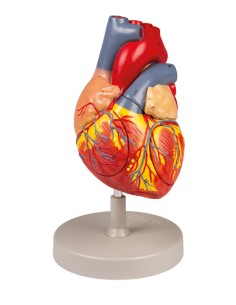

Des modèles anatomiques détaillés pour tous les besoins

Du crâne en 22 parties à verrouillage magnétique aux modèles de colonne vertébrale, des modèles d'articulation aux modèles de cœur, chaque pièce de notre collection est conçue pour une immersion totale dans l'étude de l'anatomie humaine. Nos modèles, réalisés à partir de scans d'os réels, garantissent une expérience tactile authentique et une fidélité de poids presque identique aux originaux.

Indispensables aux étudiants comme aux professionnels, nos modèles anatomiques sont des outils pédagogiques qui permettent d'observer les structures anatomiques avec précision, en évitant les dissections ou les études invasives. Ils sont également utiles pour expliquer les pathologies aux patients, ce qui rend la communication plus efficace et permet de gagner un temps précieux.